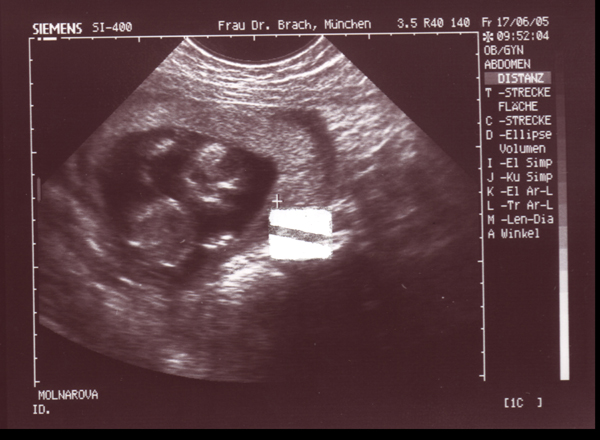

17.06.05 - 15. Woche - 9,0cm